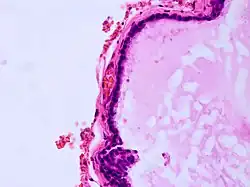

| Histopathology of colloid cyst |

A colloid cyst is a non-malignant tumor in the brain. It consists of a gelatinous material contained within a membrane of epithelial tissue. It is almost always found just posterior to the foramen of Monro in the anterior aspect of the third ventricle, originating from the roof of the ventricle. Because of its location, it can cause obstructive hydrocephalus and increased intracranial pressure. Colloid cysts represent 0.5–1.0% of intracranial tumors.[1]